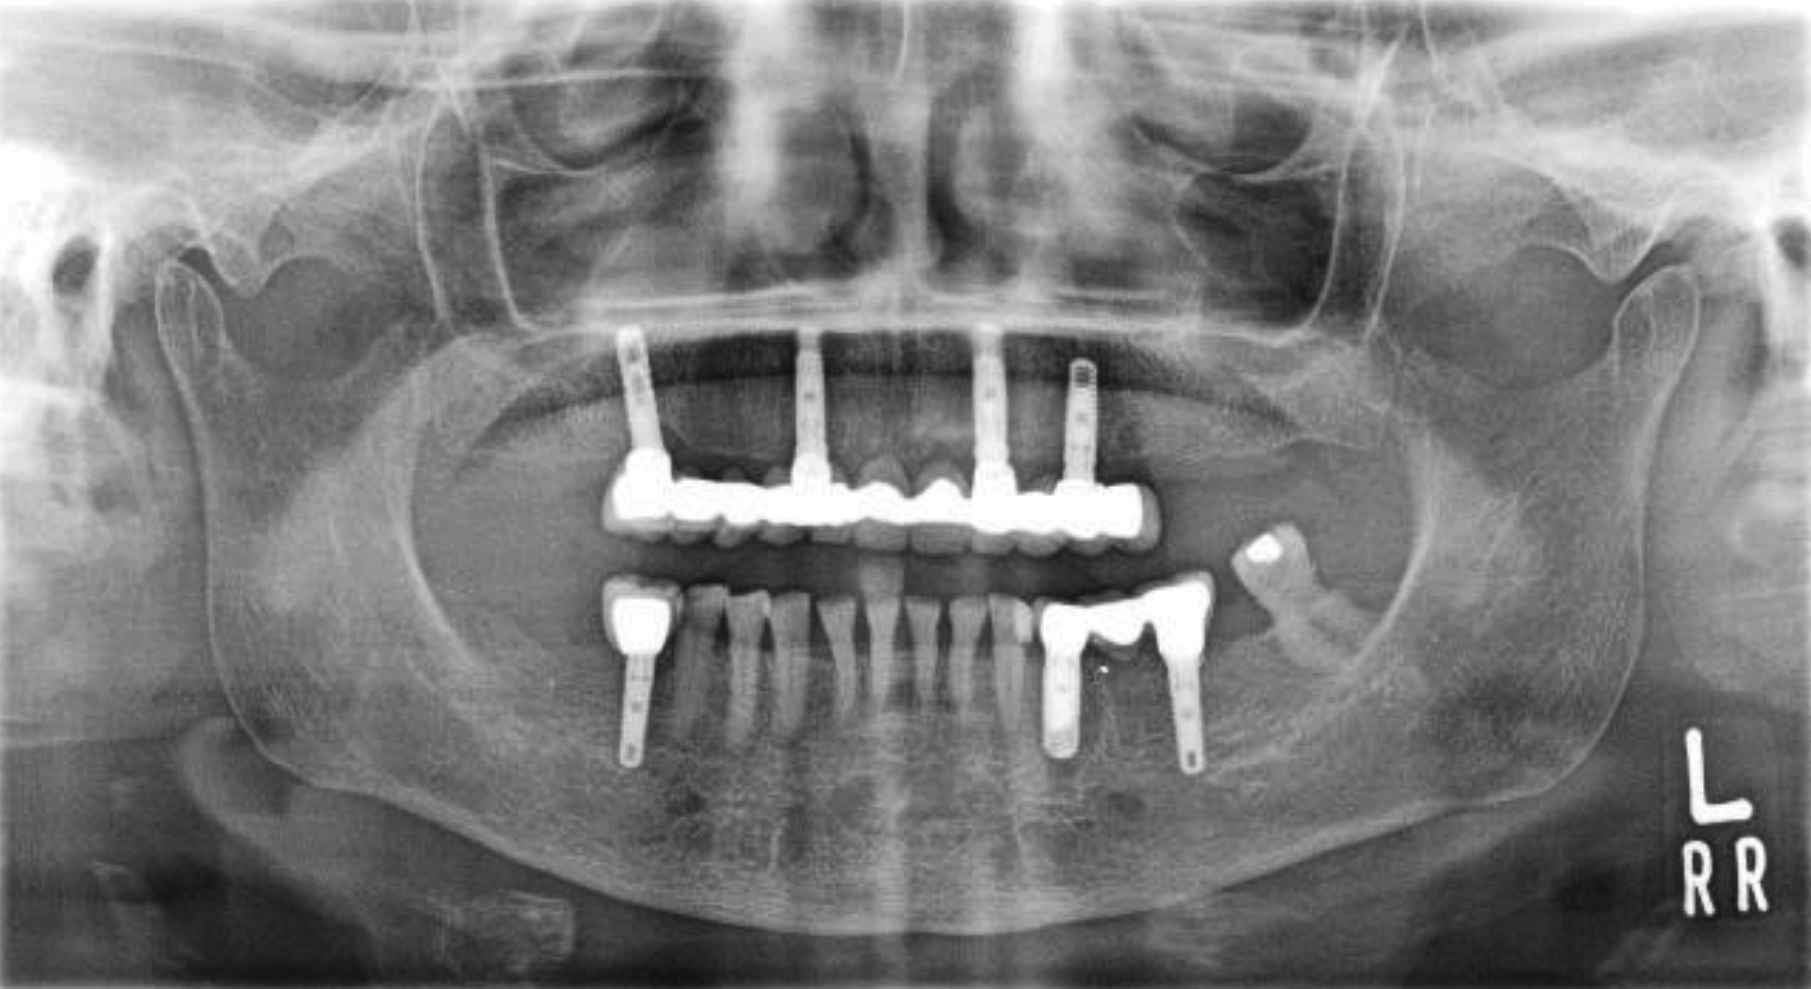

Immediate Placement and Loading of Full Arch Dental Implants in An

Immediate Placement and Loading of Full Arch Dental Implants in An Oral Bisphosphonates Dental Implants our results show that dental implant placement in patients receiving bisphosphonates does not reduce the. To analyze articles that studied patients submitted to diphosphonates therapy and who received. — javed and almas showed that the incidence of implant failure was minimal in patients using oral and intravenous. — five studies analysed intraoral bisphosphonate medication in relation with. Oral Bisphosphonates Dental Implants.

Immediate Placement and Loading of Full Arch Dental Implants in An Oral Bisphosphonates Dental Implants — five studies analysed intraoral bisphosphonate medication in relation with implant placement, three studies. — a significant adverse effect observed in patients using either oral or intravenous (iv) bps who have undergone. — javed and almas showed that the incidence of implant failure was minimal in patients using oral and intravenous. patients who are prescribed oral. Oral Bisphosphonates Dental Implants.

Immediate Placement and Loading of Full Arch Dental Implants in An Oral Bisphosphonates Dental Implants To analyze articles that studied patients submitted to diphosphonates therapy and who received. patients who are prescribed oral bisphosphonates and are not receiving regular dental care likely would benefit. — javed and almas showed that the incidence of implant failure was minimal in patients using oral and intravenous. our results show that dental implant placement in patients. Oral Bisphosphonates Dental Implants.